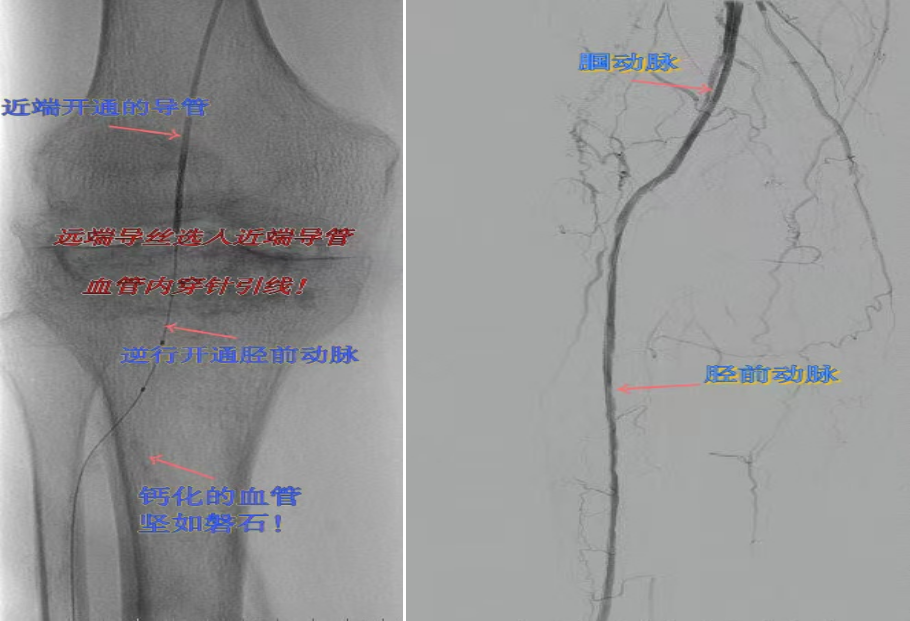

67岁女性患者,多年糖尿病、冠心病史,因右足溃烂伴凉麻疼痛长达2年就诊,此前曾接受外院介入术后血管再度闭塞。此次检查发现其股浅动脉、腘动脉至膝下血管全程闭塞,且伴有严重钙化。团队迎难而上,创新性经足背动脉逆向穿刺,耗时3小时成功贯通胫前动脉。术后当夜患者足部即感回暖,溃烂足趾疼痛显著缓解。术后结合中药外治(换药、熏洗、去腐生肌膏外敷)加速创面愈合。该患者已于出院,院外换药治疗。

影像检查:股浅动脉、腘动脉至膝下血管全程闭塞伴严重钙化。

两例患者共同凸显三大高难度治疗挑战:1.患者高龄且基础病复杂;2.血管全程多节段闭塞、钙化程度严重;3.常规顺向开通路径已被完全阻断。团队果断采用远端逆行穿刺技术,在纤细的足踝部血管建立治疗通道,实现“逆向破冰”。

“逆向开通操作技术”就像在复杂的血管迷宫中反向找“出口”。介入血管外科杨彦林副主任形象地比喻道,“该操作技术突破了传统顺向开通的技术局限,为濒临截肢的晚期糖足患者提供了宝贵的保肢新选择。”目前该方案已成为我院治疗复杂下肢动脉病变的常规手段。